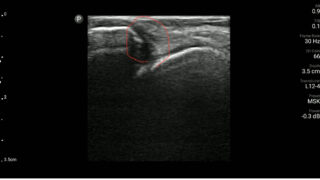

運動器エコー

外側靭帯の修復過程及びアプローチ

外側靭帯の修復過程 外側靭帯(特に前距腓靭帯)は血流が乏しく、治癒には時...